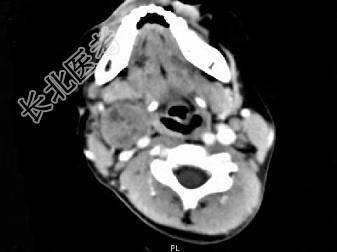

- 单项选择题女,4岁, 右侧颈部可扪及一包块约两个月,无热无痛, CT如图所示,最可能的诊断为  (    )